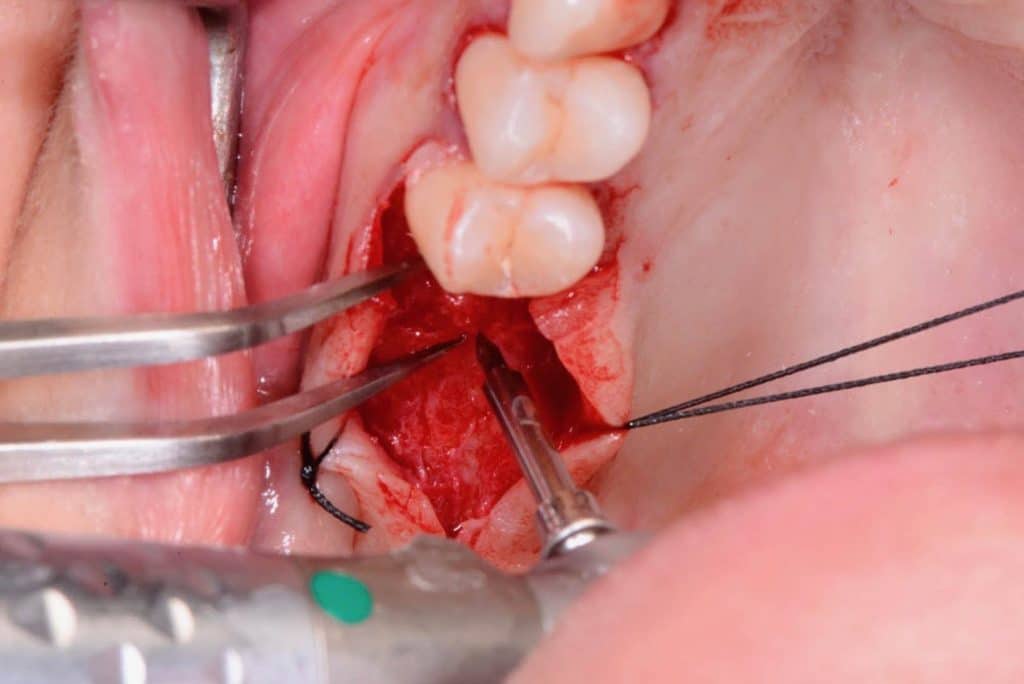

At this stage, the device is manually screwed until one can see the white stripe on the probe. Seeing that stripe means that the SinCrest has reached the depth made by the burs. The handpiece is now rotated of ½ rotation first counterclockwise and then clockwise applying a pressure axially. By repeating this “screw and unscrew” motion, the thread of the device is kept completely stationary, and an osteotomy of 0.5 mm is carried out apically.

At this stage, it is possible to screw the SinCrest again so that it will go forward of 0.5 mm apically. When the white stripe disappears, it means that the bone operculum is fractured, and it is possible to insert the bio-material for the elevation. In this case, we used Bio-Oss inserted in the sinus utilizing a carrier and pushed apically using osteotomes: it is essential not to go further than 8 mm (and 6mm in the case of the other distal site).